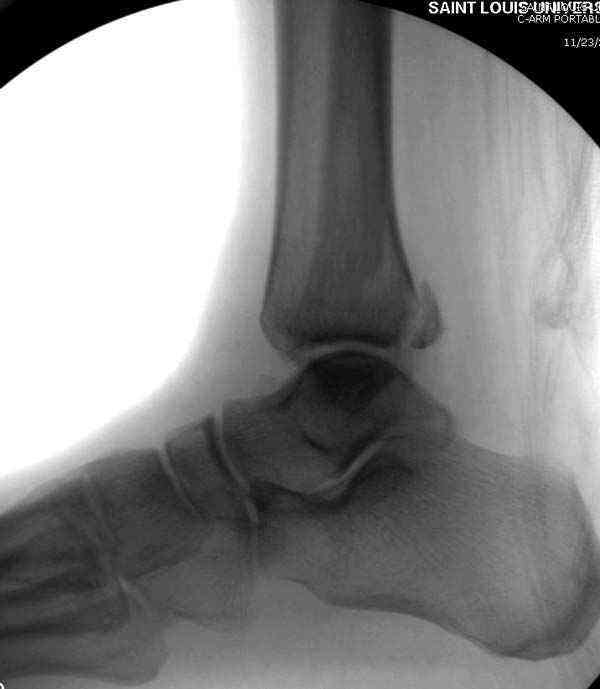

Случай прошлого года:пациентка-молодая ,крупная женщина ,30лет.Травма в начале апреля 2009г-пронационный перелом лодыжек с подвывихом стопы.Ко мне обратилась через 35 дней,прооперирована 22.05.2009г.Внутренняя лодыжка фиксирована по Веберу,наружная реконструктивной пластиной с наложением болта-стяжки.Иммобилизация "сапожок" в течении месяца,затем пригипсовано "стремя".Гипс снят 10.07.2009г

Достаточно быстрое восстановление функции.В октябре 2009г-почувствовала боль,в области рубца над гайкой открылся свищ.На Р-граммах-консолидация переломов и смещение гайки по стяжке.10.11.2009г-конструкции удалены,санация,заживление ран.В настоящее время пациентку ничего не беспокоит.На операции-раскручивание гайки-болталась на конце стяжки.Вопросы:какой механизм раскручивания и что я неправильно сделал?Свои версии:1)в области синдесмоза успела образоваться рубцовая ткань,которая при движении в суставе"пружинила",поскольку голеностопный сустав является спиральным, то и биомеханика подобна кривошипному механизму.2)Реконструктивная пластина не "реконструировалась" по форме лодыжки.Наложил,как есть.То есть подпружинивала сама пластина.Ну,это мои догадки.Что нужно,чтобы избегать впредь таких,пусть и не "страшных"осложнений:Рассверливать через лодыжку область синдесмоза?Ставить шайбу-гровер?Тщательно моделировать пластину?Прилагаю сравнительные снимки-сразу после операции и перед удалением конструкции.

Визуально никаких вопросов по репозиции не было.Да и на основании чего сомнения,что наружная лодыжка не полностью репонирована или прорезалась проволка ???Я не вижу...Снимок после репозиции справа.

Раз ,есть желание посмотреть другую проекцию выкладываю-ну лучшего качества нет...